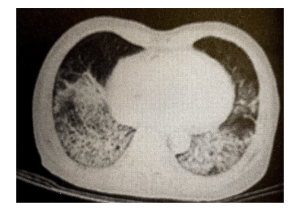

经过近10年的应用,IDSA-2007的主次要标准在被不断地验证和冲刷。在此基础上,中华医学会呼吸病学分会制定了《中国成人社区获得性肺炎诊断和治疗指南(2016年版)》(表2),并对重症肺炎重新进行了界定。临床上强调了有肺部感染的影像学表现,对合并脓毒症休克或需机械通气最关注,而氧合指数定的是小于250mmHg。如图1,临床就更符合重症肺炎而不是ARDS。

图1 胸部CT示双肺病变